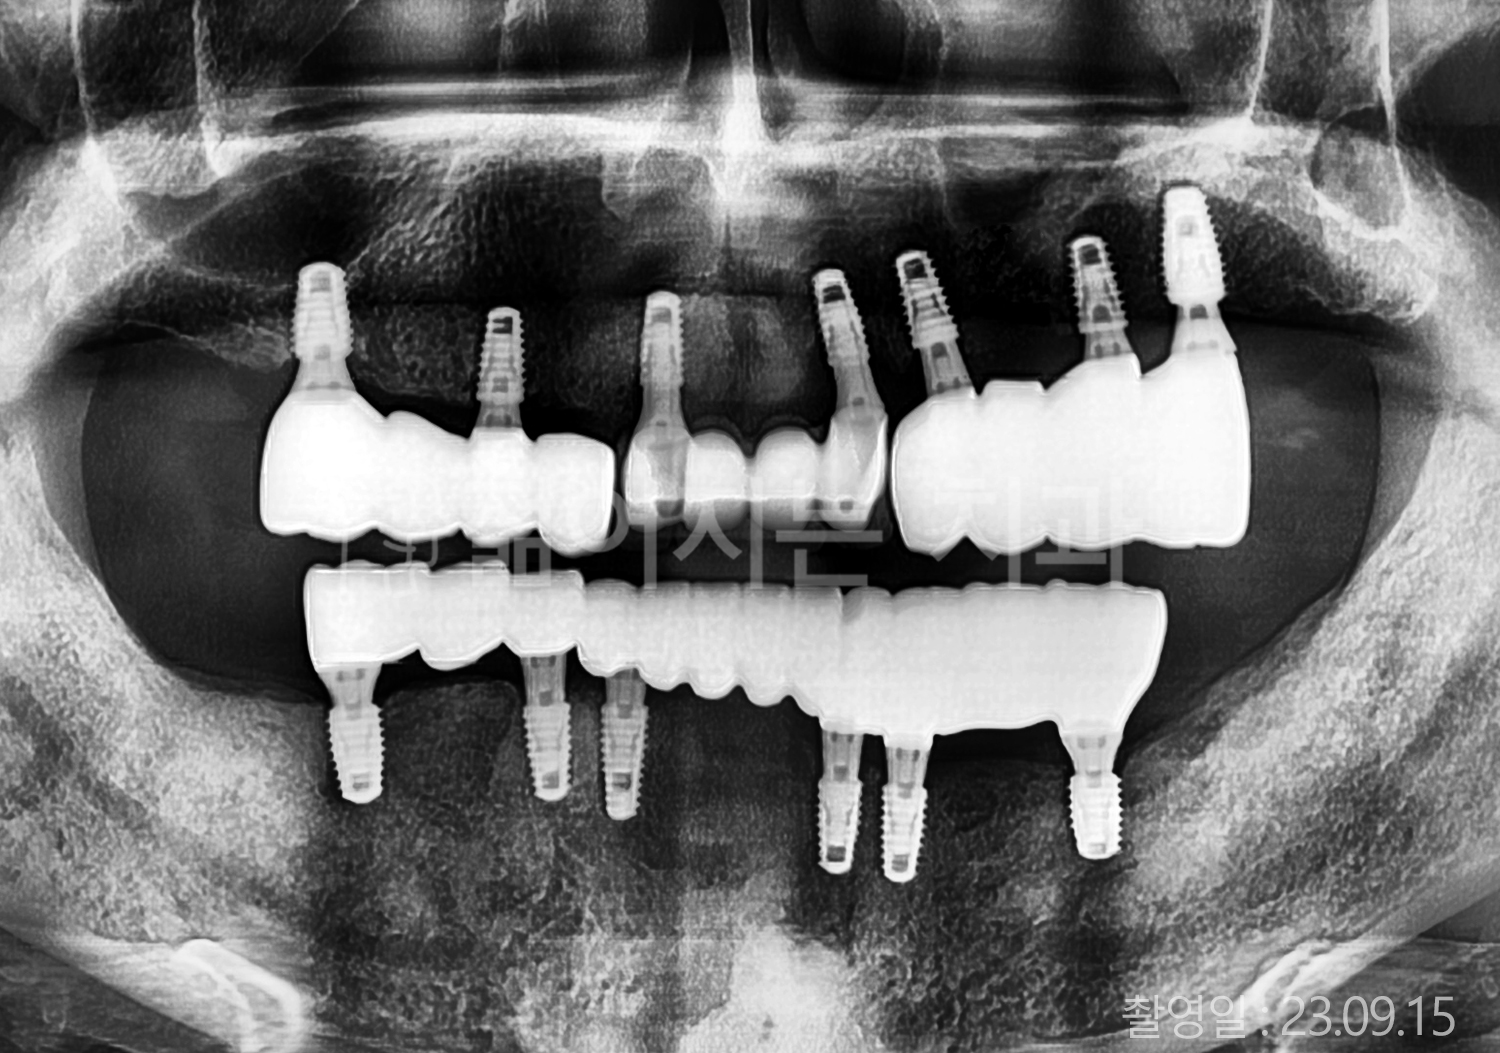

• 50대 고혈압, 고지혈증 전체치아 10개 이상 임플란트